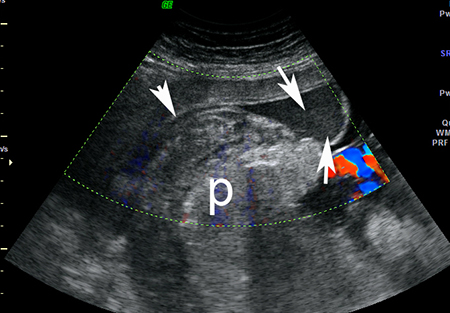

Imagem de ultrassonografia de descolamento da placenta: a placenta normal está marcada com 'p'; área de descolamento indicada por setas brancas

Do acervo de Dr Y Oyelese; usado com permissão